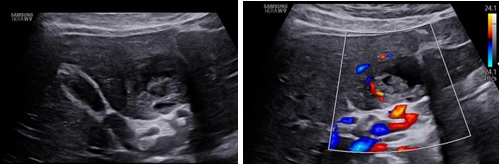

Hình ảnh siêu âm:

Hình 1, 2: Túi thai nằm ở hạ phân thùy IVb gan trái, giữa dây chằng tròn và túi mật. Tăng sinh mạch máu quanh túi thai, túi thai nằm rất sát một nhánh của tĩnh mạch cửa trái.